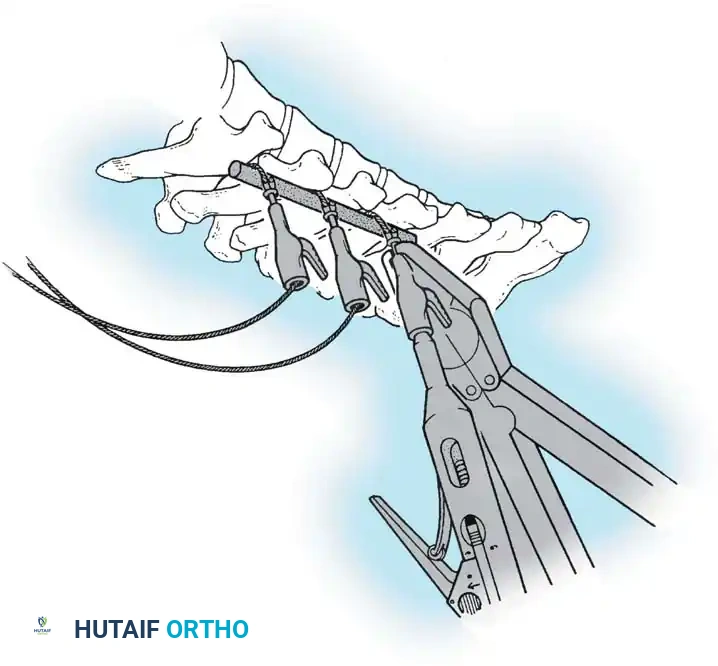

Deep Subperiosteal Dissection

- Cartilaginous Cap Incision: Incise the cartilaginous cap overlying the spinous processes precisely in the midline. Note that in severe scoliosis, the midline may be significantly deviated due to apical vertebral rotation.

- Cobb Elevation: Utilizing a Cobb elevator combined with electrocautery, expose the spinous processes subperiosteally. Move the cartilaginous caps and attached paraspinal muscles laterally.

- Direction of Dissection: It is anatomically advantageous to dissect from caudad to cephalad. The short rotator muscles (multifidus and rotatores) and ligaments of the spine attach obliquely, pointing superomedially. Sweeping upward works with the grain of these fibers, allowing for a cleaner, faster subperiosteal release.

- Maintaining Tension: As the exposure deepens, sequentially advance the Weitlaner or Cerebellar retractors. Constant, firm retraction is the surgeon's best tool for passive hemostasis.

Lateral Exposure and Hemostasis

- Transverse Process Exposure: Extend the subperiosteal dissection laterally, first exposing the facet joints, and then continuing out to the tips of the transverse processes bilaterally.

- Segmental Vessels: As you dissect lateral to the facet joints, you will encounter the posterior branches of the segmental vessels. These must be meticulously identified and coagulated with bipolar or monopolar cautery to prevent insidious bleeding.

- Facet Cleaning: Use a sharp curet and a pituitary rongeur to completely excise the facet capsules and clean the interspinous ligaments.

Clinical Pearl: Always direct your curet from the midline laterally when cleaning the facet joints. This directional force ensures that if the instrument slips, it moves safely away from the spinal canal, preventing catastrophic dural tears or iatrogenic spinal cord injury.